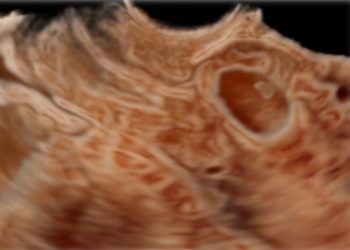

How To Do Agosto 2021: Cesarean Scar Pregnancy

Cari soci, questo mese un nuovo video "How to do", sulla diagnosi ecografica di gravidanza su cicatrice di pregresso taglio...